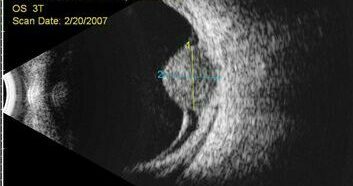

Szemészeti ultrahang

A szem belső területeinek ultrahangos vizsgálata pl. üvegtesti homályok, vérzések, daganatok esetén.